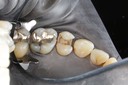

Gary Umeda #13-14 prep

Gary Umeda #13-14 finish

Gary Umeda #14 lingual foil